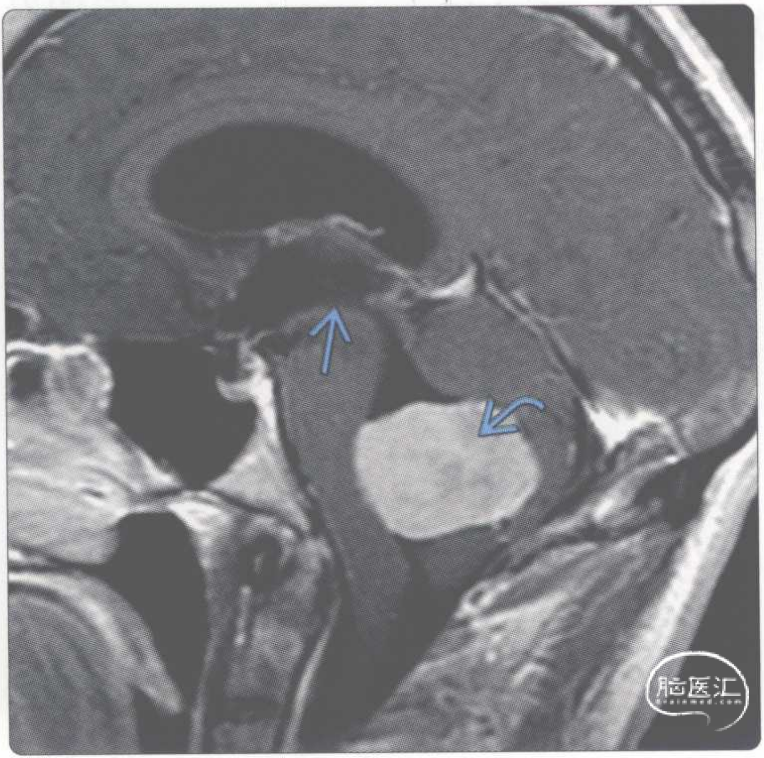

【影像时间·265】一位脑膜瘤患者